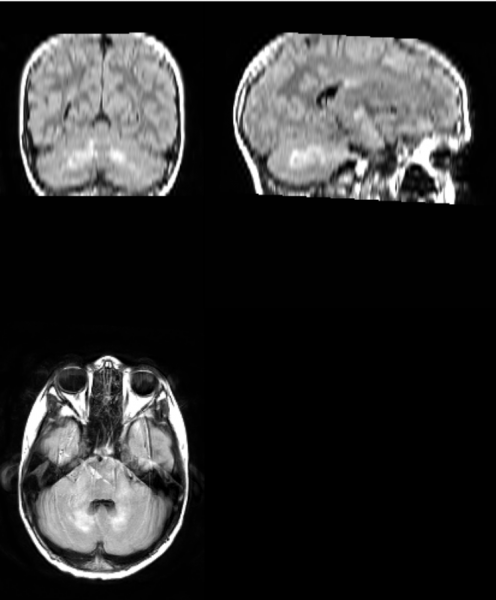

FLAIR image of an neurofibromatosis 1 patient’s brain. Bright white spots are representative of UBOs. (Photo courtesy of VUIIS, Laurie Cutting and Emily Harriott)

The best way to see many of the features of the disease is to do FLAIR imaging (a type of magnetic resonance imaging) on the brains of patients. In FLAIR images of neurofibromatosis 1 patients, there often are abnormally bright spots that likely indicate the presence of fluid between layers of myelin sheaths—the insulation surrounding certain nerve cells—which may contribute to the cognitive deficits observed in patients.